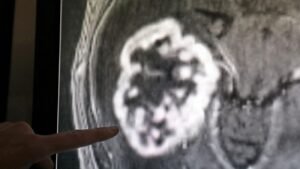

Kopf-Hals-Tumoren betreffen in Rheinland-Pfalz mehr Männer als Frauen – neue Zahlen zeigen aber eine vorsichtig positive Entwicklung....